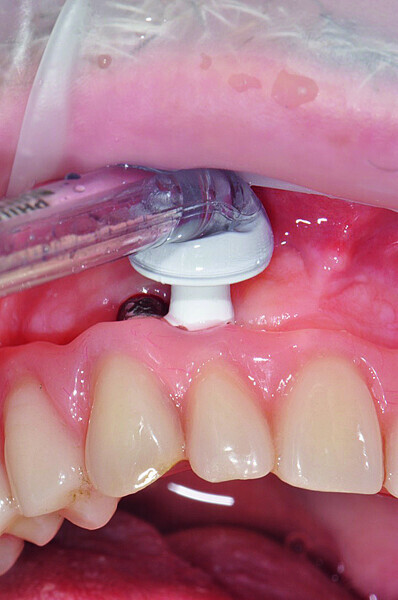

Fig. 4a: Peri-implant home care with a) AirFloss (Philips), b) X-Floss (ROEN) and c) interdental brush (TePe).

Fig. 4b: Peri-implant home care with a) AirFloss (Philips), b) X-Floss (ROEN) and c) interdental brush (TePe).

Fig. 4c: Peri-implant home care with a) AirFloss (Philips), b) X-Floss (ROEN) and c) interdental brush (TePe).